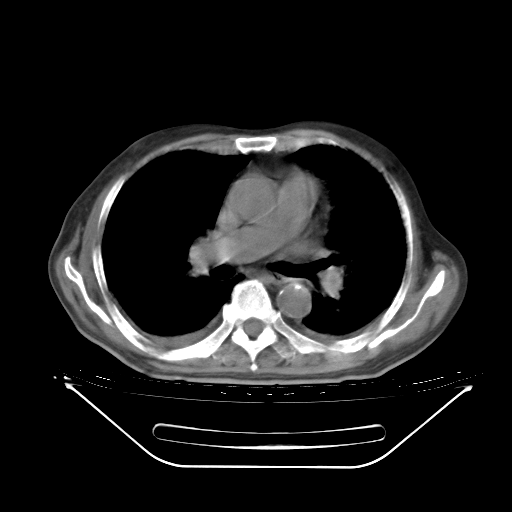

今天复查肺部CT,发现双肺广泛磨玻璃样改变。所以我把3月19日和5月9日相隔50天的肺部CT上传。请大家会诊。

5月9日肺部CT(在4月27日齐鲁医院肺部CT描述部分肺组织磨玻璃样改变,12天后肺组织广泛磨玻璃样改变)

2009年5月9日肺部CT